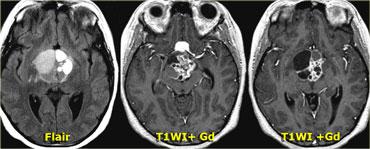

Sọ hầu u (Craniopharyngioma)

Sọ hầu u là bệnh lý thứ ba trong số ba bệnh lý có nguồn gốc từ biểu mô khe Rathke.

Về mặt kỹ thuật, đây là các khối u lành tính, nhưng khác với nang khe Rathke, chúng có thành dày và xâm lấn tại chỗ.

Về đại thể, đây là một khối phức tạp với nhiều nốt ở nền não, len lỏi dọc theo các khe não.

Thông thường, khối u không thể được cắt bỏ hoàn toàn.

Hình ảnh bên phải cho thấy một nang thành dày là một phần của sọ hầu u.

Trong hơn 50% trường hợp, sọ hầu u có hình ảnh đặc trưng bệnh lý (pathognomonic).

Trên các hình ảnh chuỗi xung T1W mặt phẳng đứng dọc không và có tiêm thuốc tương phản từ, có thể nhận thấy tuyến yên bị chèn ép.

Có một khối lớn trong hố yên và trên hố yên với các thành phần dạng nang, thành phần ngấm thuốc cũng như vôi hóa.

Các dấu hiệu này ở trẻ em gần như là đặc trưng bệnh lý của sọ hầu u (có thể chỉ cần chẩn đoán phân biệt với u bì – dermoid).

Hình ảnh mặt phẳng đứng ngang (coronal) của cùng một khối.

Và hình ảnh mặt phẳng ngang (axial).

CT không tiêm thuốc cản quang cho thấy các vôi hóa rõ ràng hơn.

Sau khi tiêm thuốc cản quang tĩnh mạch, toàn bộ phạm vi của tổn thương và các thành phần dạng nang của nó trở nên kém rõ ràng hơn nhiều.